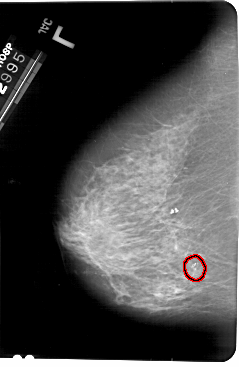

A_1496_1.LEFT_CC

LEFT_CC LINES 5491 PIXELS_PER_LINE 3571 BITS_PER_PIXEL 12 RESOLUTION 43.5 OVERLAY

FILE: A_1496_1.LEFT_CC.OVERLAY

TOTAL_ABNORMALITIES 1

ABNORMALITY 1

LESION_TYPE CALCIFICATION TYPE AMORPHOUS DISTRIBUTION CLUSTERED

ASSESSMENT 2

SUBTLETY 5

PATHOLOGY BENIGN

TOTAL_OUTLINES 1